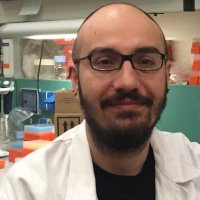

Αγαθαγγελίδης Ανδρέας, Επιστημονικός Υπεύθυνος του ερευνητικού έργου με τίτλο: «CLLon | Ανοσογενετική και λειτουργική ανάλυση του Β κυτταρικού υποδοχέα στη Μονοκλωνική Β λεμφοκυττάρωση και τη Χρόνια Λεμφοκυτταρική Λευχαιμία: προεκτάσεις για την οντογένεση της νόσου»

Το πρόγραμμα CLLon στοχεύει στην κατανόηση των διαδικασιών που σχετίζονται με το Β κυτταρικό υποδοχέα (ΒΚΥ), οι οποίες συμβαίνουν κατά τη φυσική εξέλιξη της Χρόνιας Λεμφοκυτταρικής Λευχαιμίας (ΧΛΛ) και συνεισφέρουν στην οντογένεση και την πρόοδο της νόσου μέσω της εφαρμογής ανοσογενετικών και λειτουργικών μελετών του…